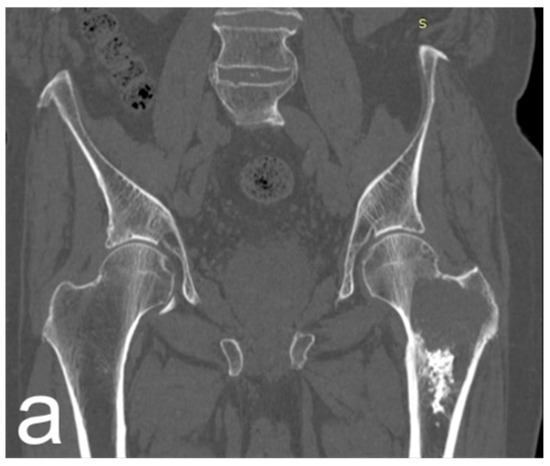

Characteristics of oncological patients are shown in Table 1. Among 15 procedures in tumor patients, one-third was performed for primary bone or soft tissue tumors, with chondrosarcoma representing the most frequent histotype, accounting for 80% of primary tumors and 100% of primary bone tumors (Figure 1).

Figure 1.

(a) Male, 84 years old, affected by dedifferentiated chondrosarcoma of the left proximal femur; CT coronal reconstruction of the proximal femur. (b) Axial CT scan shows extraosseous extension of the tumor. (c) Resection and reconstruction with a cemented proximal femur megaprosthesis were performed. The patient lived for 10 years (122 months) after surgery with no tumor recurrence and was able to walk with the aid of a cane. He died at 122 months due to a concomitant disease.